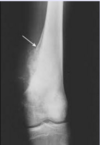

Osteosarcoma arises in the […] of long bones, often around the knee.

Osteosarcoma arises in the metaphysis of long bones, often around the knee

i.e. distal femur or proximal tibia